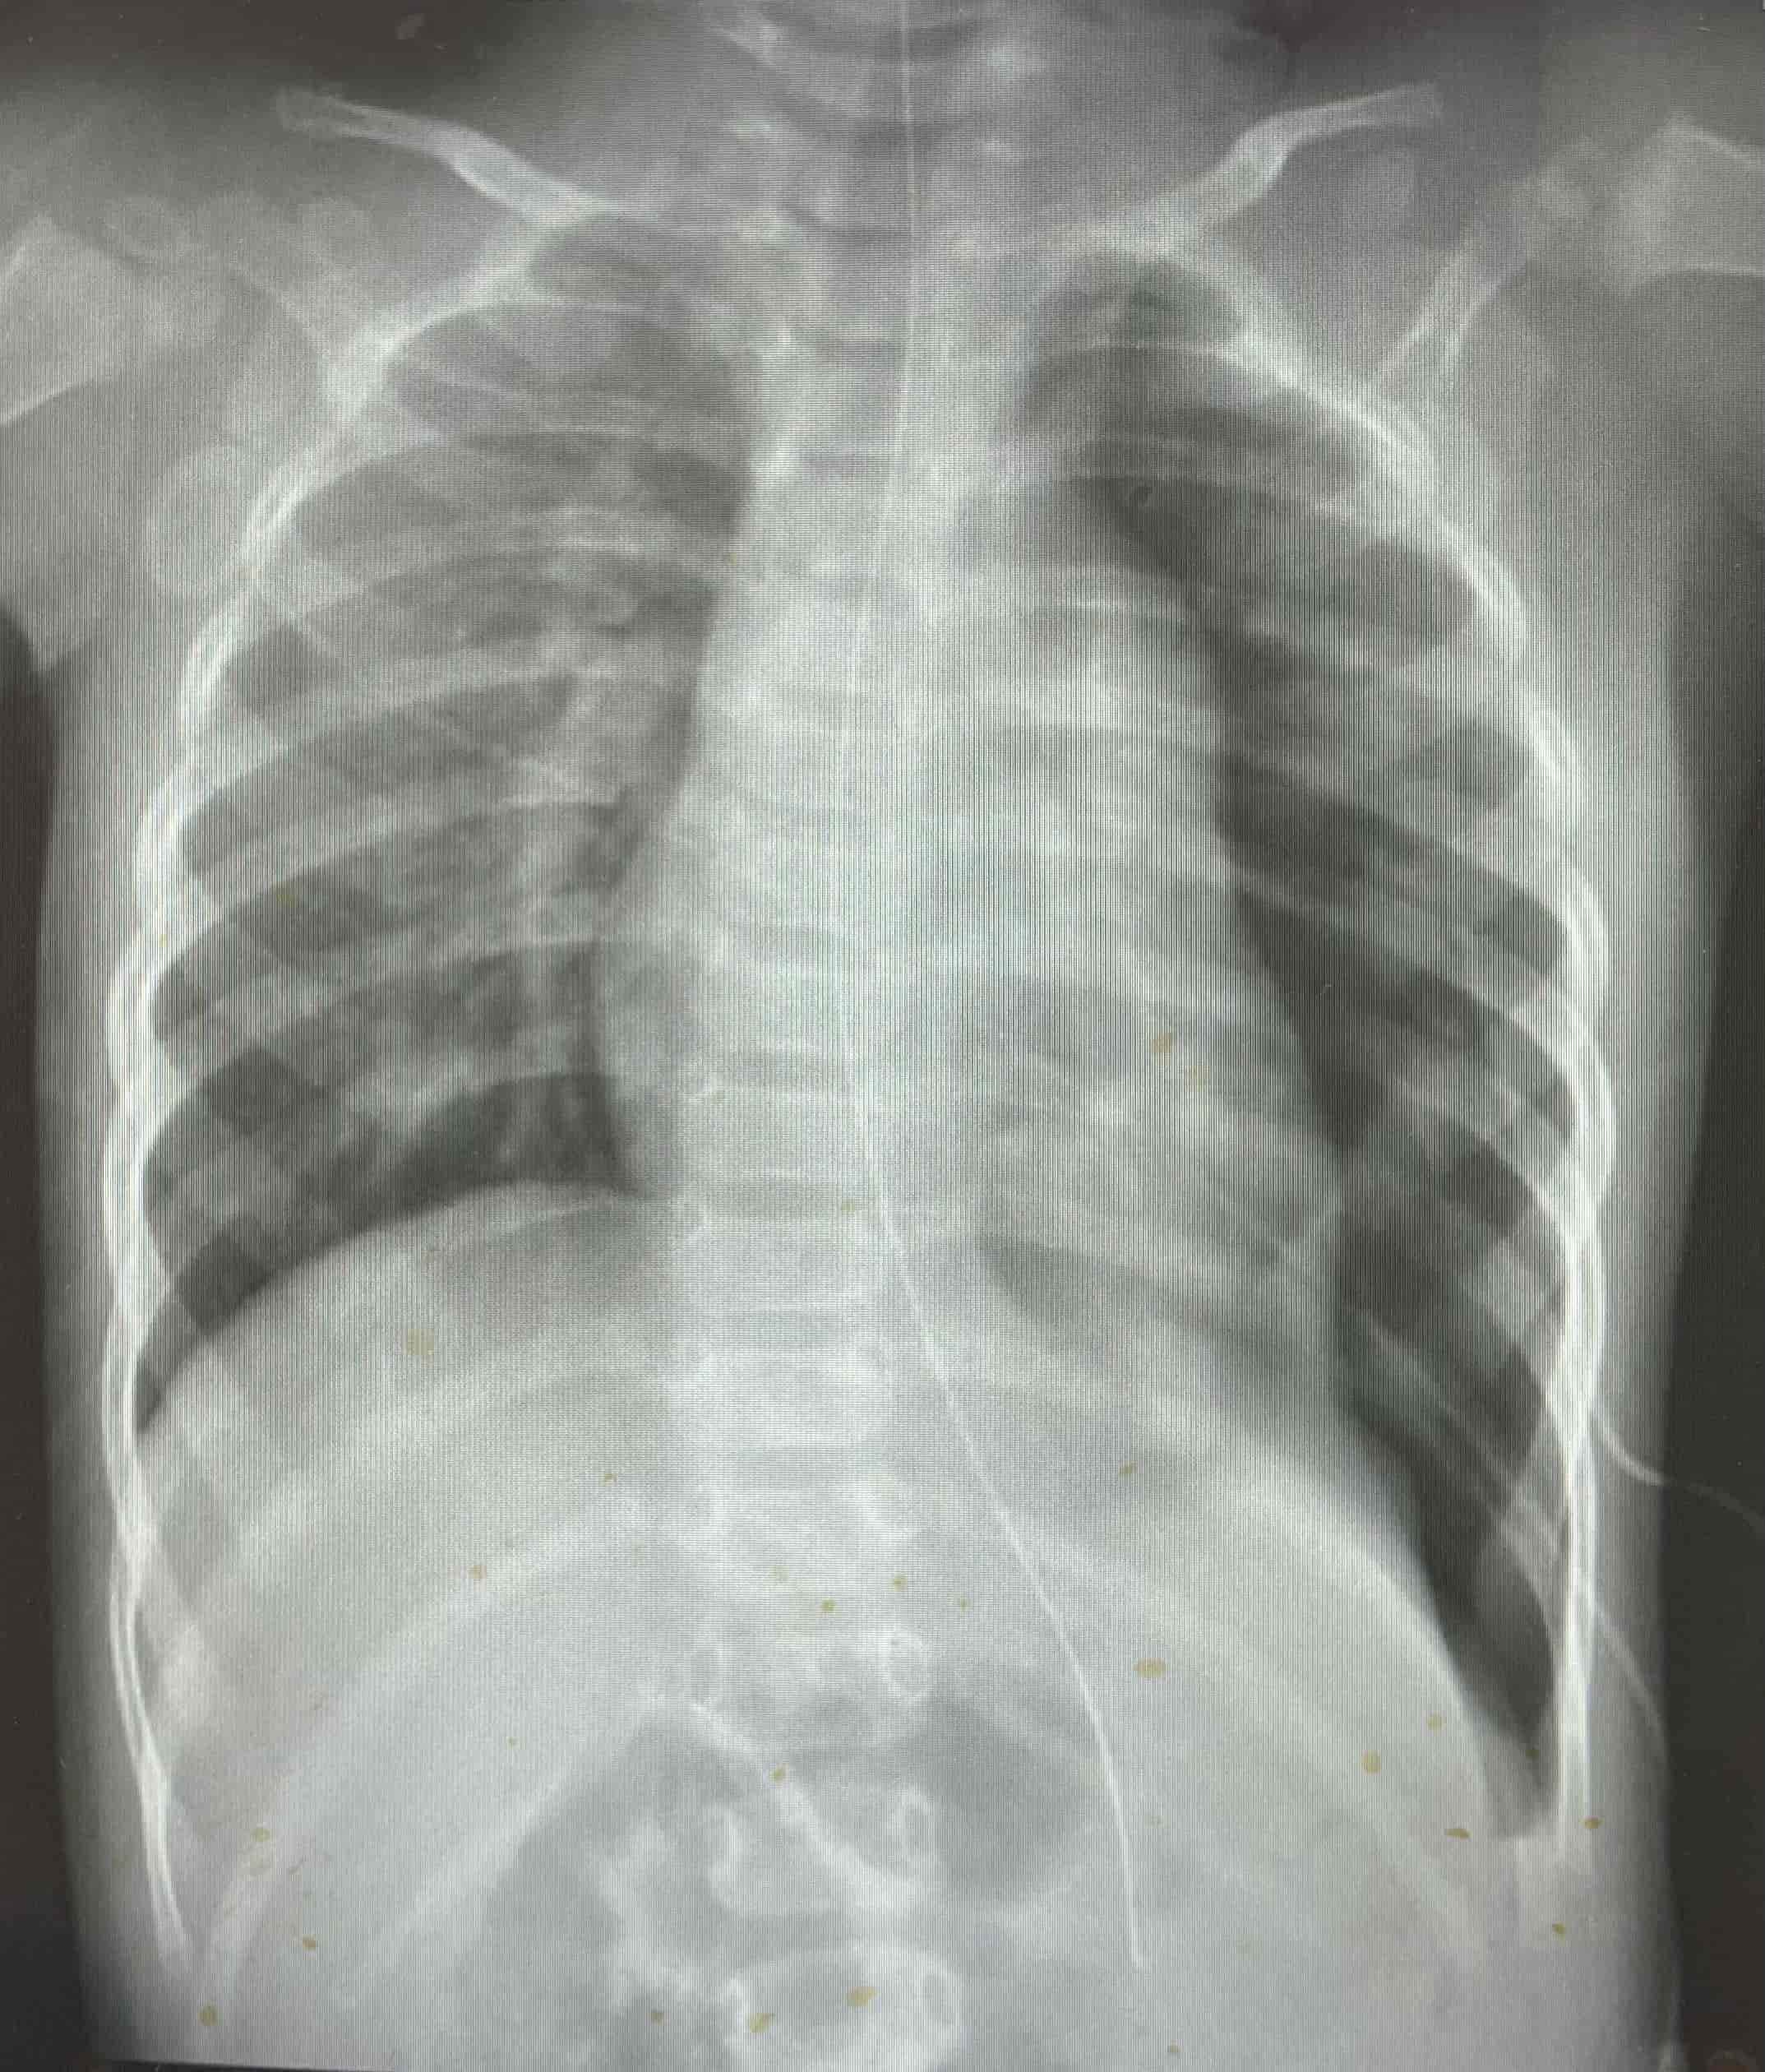

"Tuvimos que analizar rápidamente diagnósticos diferenciales para llegar al punto de lo que le estaba causando todos estos síntomas a la paciente. Se le realizaron placas de pecho y de abdomen, y ahí nos percatamos, que esta paciente teníauna herniadiafragmática y que gran parte de su estómago estaba distendido y dentro del hemitórax izquierdo, desplazando hacia el lado derecho del pecho las estructuras mediastinales. Fue entonces que llegamos a la confirmación del diagnóstico", detallaron.

"El estómago estaba muy distendido y lleno de líquido y aire, que empujaba las estructuras mediastinales y esto provocaba una disminución en la cantidad de sangre que llegaba al cuerpo. El radiólogo confirmó el diagnóstico , quien nos informó que tenía un gastrotórax a tensión, y esto demandó rápido el tratamiento de descompresión con un tubo nasogástrico", establecieron.

Médicos salvan la vida de infante con hernia diafragmática y gastrotórax a tensión  Placa lateral portable, se demuestra la hernia diafragmática. Médicos salvan la vida de infante con hernia diafragmática y gastrotórax a tensión  Radiografía de pecho y abdomen, luego de tratamiento con tubonasogástrico. Se demuestra mejoría marcada en desplazamiento deestructuras mediastinales. Médicos salvan la vida de infante con hernia diafragmática y gastrotórax a tensión  Placa de pecho portable luego de reparación quirúrgica del diafragma.

Médicos salvan la vida de infante con hernia diafragmática y gastrotórax a tensión  Placa de pecho portable luego de reparación quirúrgica del diafragma.